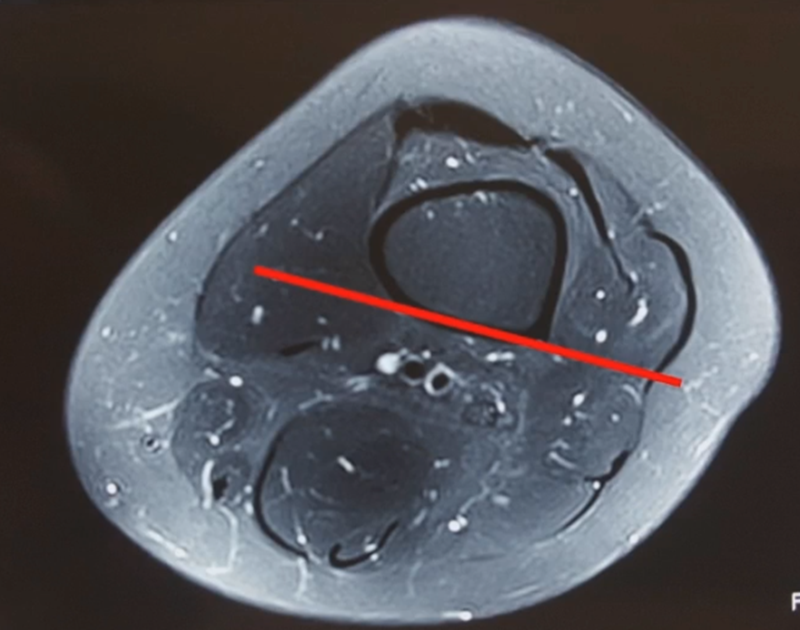

3、选择合页位置和截骨线

合页点的选择与HTO一样,通常需要尽可能接近畸形部位,既要有很好的骨质结构,还要有坚韧的软组织覆盖,以保证稳定性和术后有良好的血运。合页宽度不宜太长,通常保留在5mm。

合页点定位有两种方法,一种为定位在股骨外后髁上缘2mm位置,通常将此区域叫做“鹰嘴区”,以此为解剖标记法来定位合页点。

另一种通过导针从截骨入点向股骨外后髁后缘打出一条切线,此切线与外侧骨皮质的交点,也可作为合页点,这种方法称为导针法。这两种方法在手术之中是可以互为验证的。

合页点处于松质骨区,易形变区,如选择周边区域较脆易折断。另外合页点后方有小腿三头肌的附着点,有很好的的软组织和血运,综合来说作为合页非常合理。